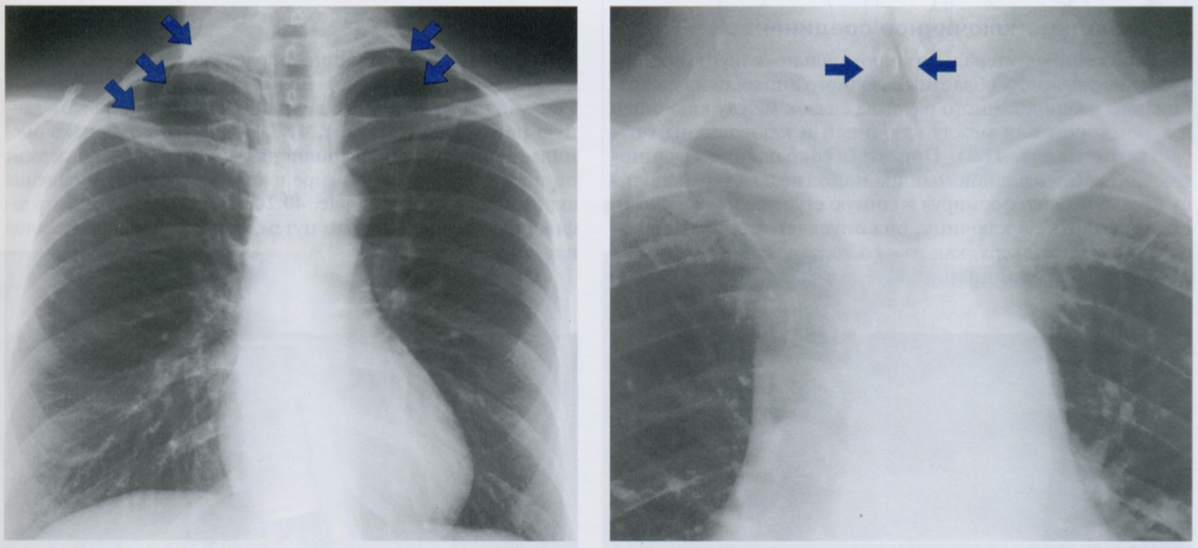

Как Вы оцените объекты отмеченные на снимке, принимая во внимание, что клиника и снимок никак нет коррелируют?

ЗПП - задняя прямая проекция и БП - боковая проекция

То есть, вероятнее всего, это артефакты. Какие?

Стрелками на первом снимке отмечены заплетенные и распущенные волосы, которые приводят к появлению артефатков, которые имитируют восходящий пневмомедиастинум или подкожную эмфизему.

На втором снимке мы видим ампутационную культю руки в БП, которая выглядит как веслообразное затемнение на уровне проекции верхнего средостения. Может имитировать новообразование.